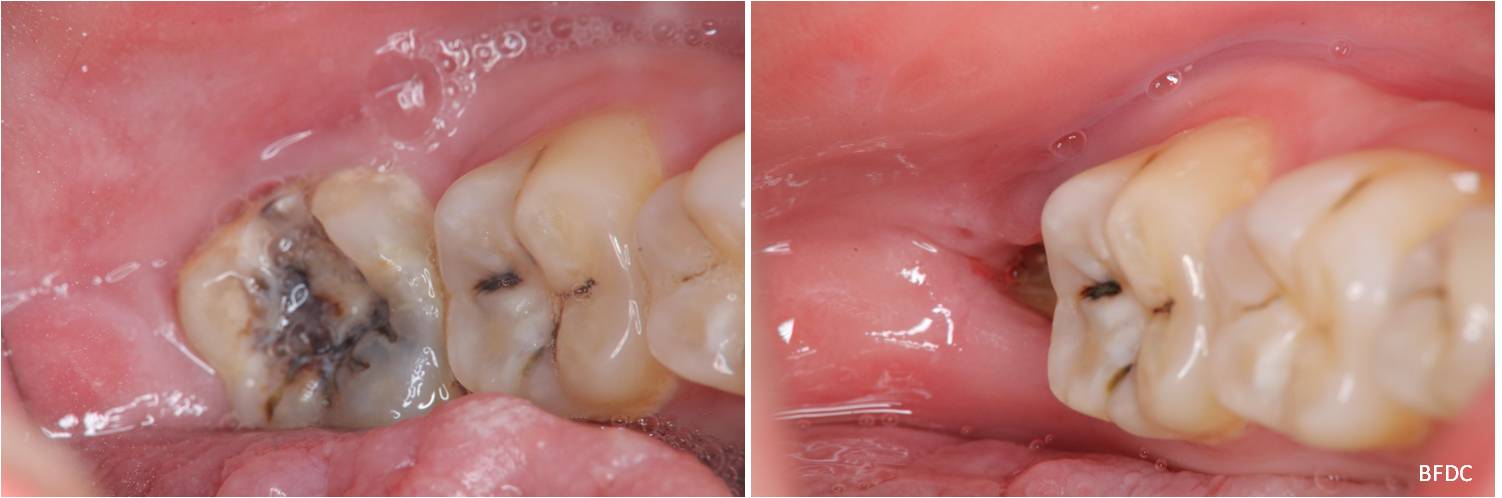

拔牙後傷口處理-阻生齒蛀牙-#38

口腔外科

拔牙後傷口處理